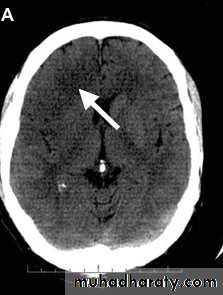

Early infarction (generally less than six hours after onset) - the CT changes are difficult to detect for the untrained eye. They include (Figure 1a):

Loss of grey/white matter differentiation

Loss of definition of the basal ganglia

Loss of sulcal pattern.

Figure 1a: Early right frontal infarct. Some loss of sulcal pattern on the right compared with the left.